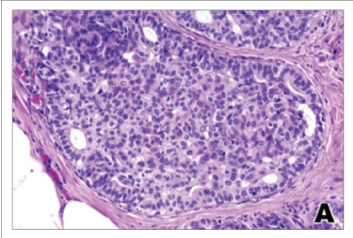

Carcinoma Ductal In Situ

O Carcinoma Ductal In Situ (CDIS) é uma lesão precursora do câncer de mama, caracterizada pela proliferação de células neoplásicas dentro dos ductos mamários sem a ruptura da membrana basal. Esta condição pode evoluir para câncer invasivo se não tratada, com um risco de 14% a 46% em 10 anos.

O seu diagnóstico ocorre através de exames de rastreamento, como mamografias, que frequentemente revelam microcalcificações irregulares.

O tratamento geralmente envolve cirurgia, que pode ser uma setorectomia ou mastectomia, dependendo da extensão da lesão. A margem cirúrgica recomendada é de pelo menos 2mm. Já a biópsia do linfonodo sentinela, não possui recomendação de rotina, mas pode ser considerada em pacientes de alto risco. Para os pacientes submetidos à setorectomia, é indicado a radioterapia, que reduz em 50% as recidivas locais.